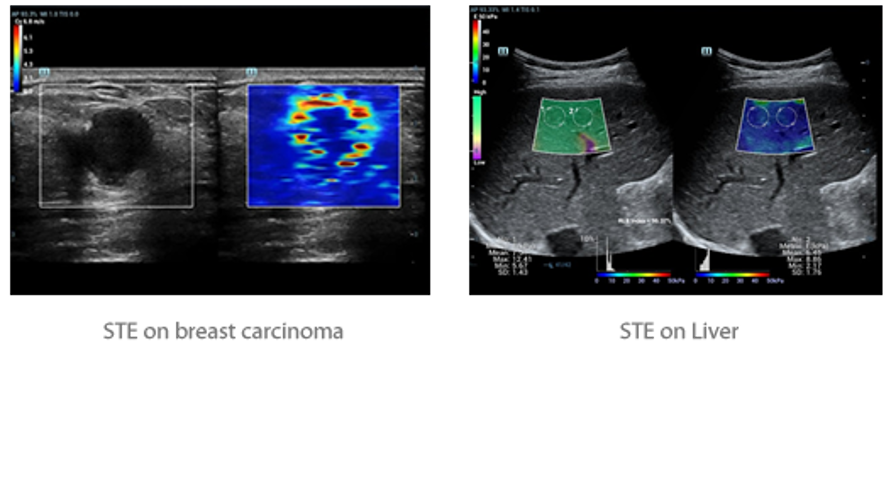

Fin dalla sua fondazione Mindray esplora continuamente nuovi modi per migliorare l'affidabilit├Ā diagnostica. Equipaggiata con la pi├╣ rivoluzionaria tecnologia ZONE Sonography?, la nuova piattaforma ZST+ di Resona 7 porta la qualit├Ā dell'immagine ecografica ad un livello superiore con l'acquisizione per zone e l'elaborazione dei dati canale.

Oltre alla qualit├Ā delle immagini di livello eccellente, Resona 7 migliora anche le capacit├Ā di ricerca clinica il rivoluzionario V Flow per la valutazione emodinamica vascolare, e l'acquisizione piani pi├╣ intelligente dal set di dati 3D per la diagnosi del sistema nervoso centrale fetale. Combinando il pi├╣ intuitivo funzionamento multi-touch basato su gesti e tutte le caratteristiche cliniche essenziali, Resona 7 sta veramente portando nuove tendenze nellŌĆÖinnovazione dellŌĆÖecografia.